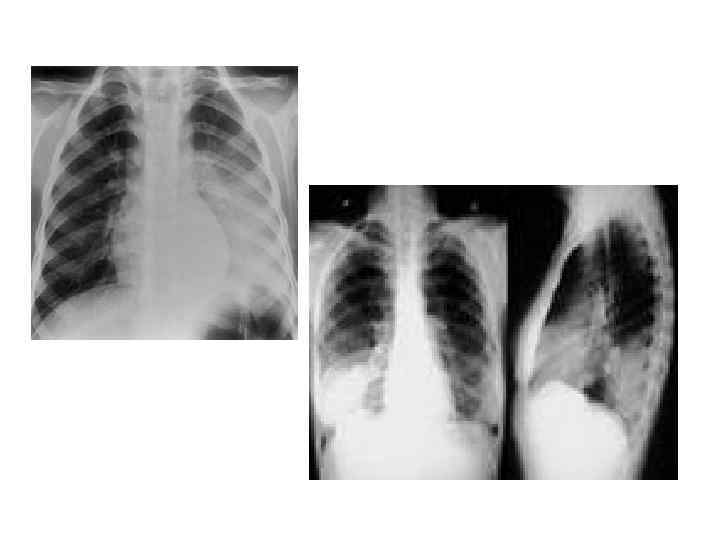

Инструментальные методы исследования • Рентгенография грудной клетки: массивное затемнение всей доли при долевой пневмонии. Рентгенологическая картина очаговой пневмонии характеризуется затемнением, соответствующим очагу воспаления. • Бронхоскопия с биопсией по показаниям; • ЭКГ, УЗИ сердца по показаниям;